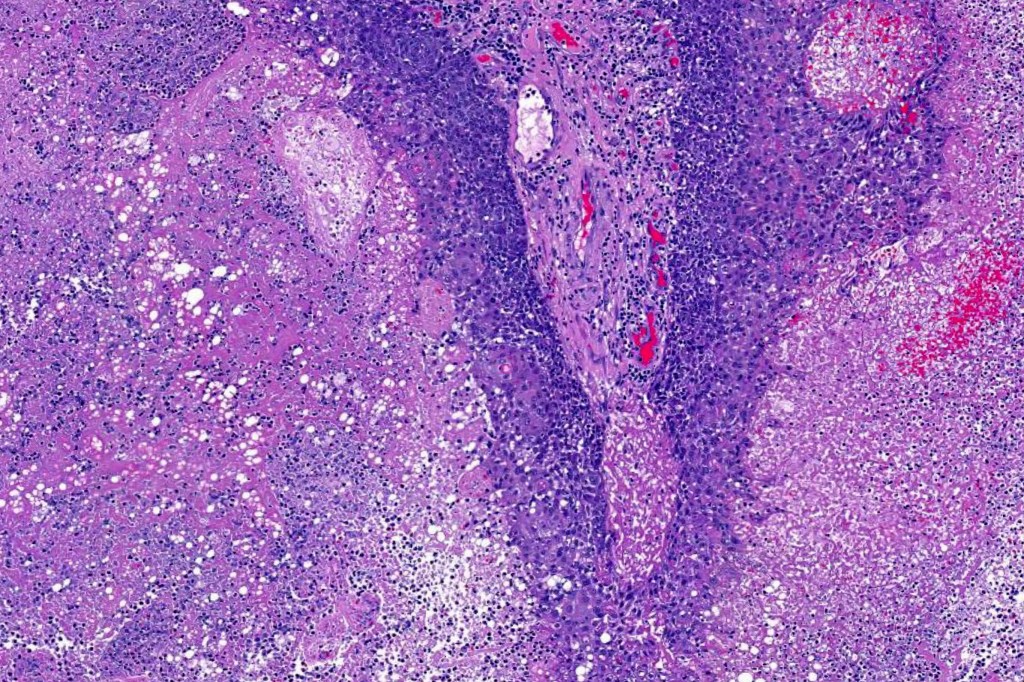

Histological features

•Well differentiated lobular growth pattern though to a poorly differentiated tumor often showing a diffuse, infiltrating border which may extend into the subcutaneous fat

•Peripheral palisading with retraction artifact and mucin deposition as seen in basal cell carcinoma is not present

•Comedo type necrosis commonly present

Sebaceous carcinoma from a patient with Muir-Torre syndrome kindly shared by Dr. Antonina Kalmykova.